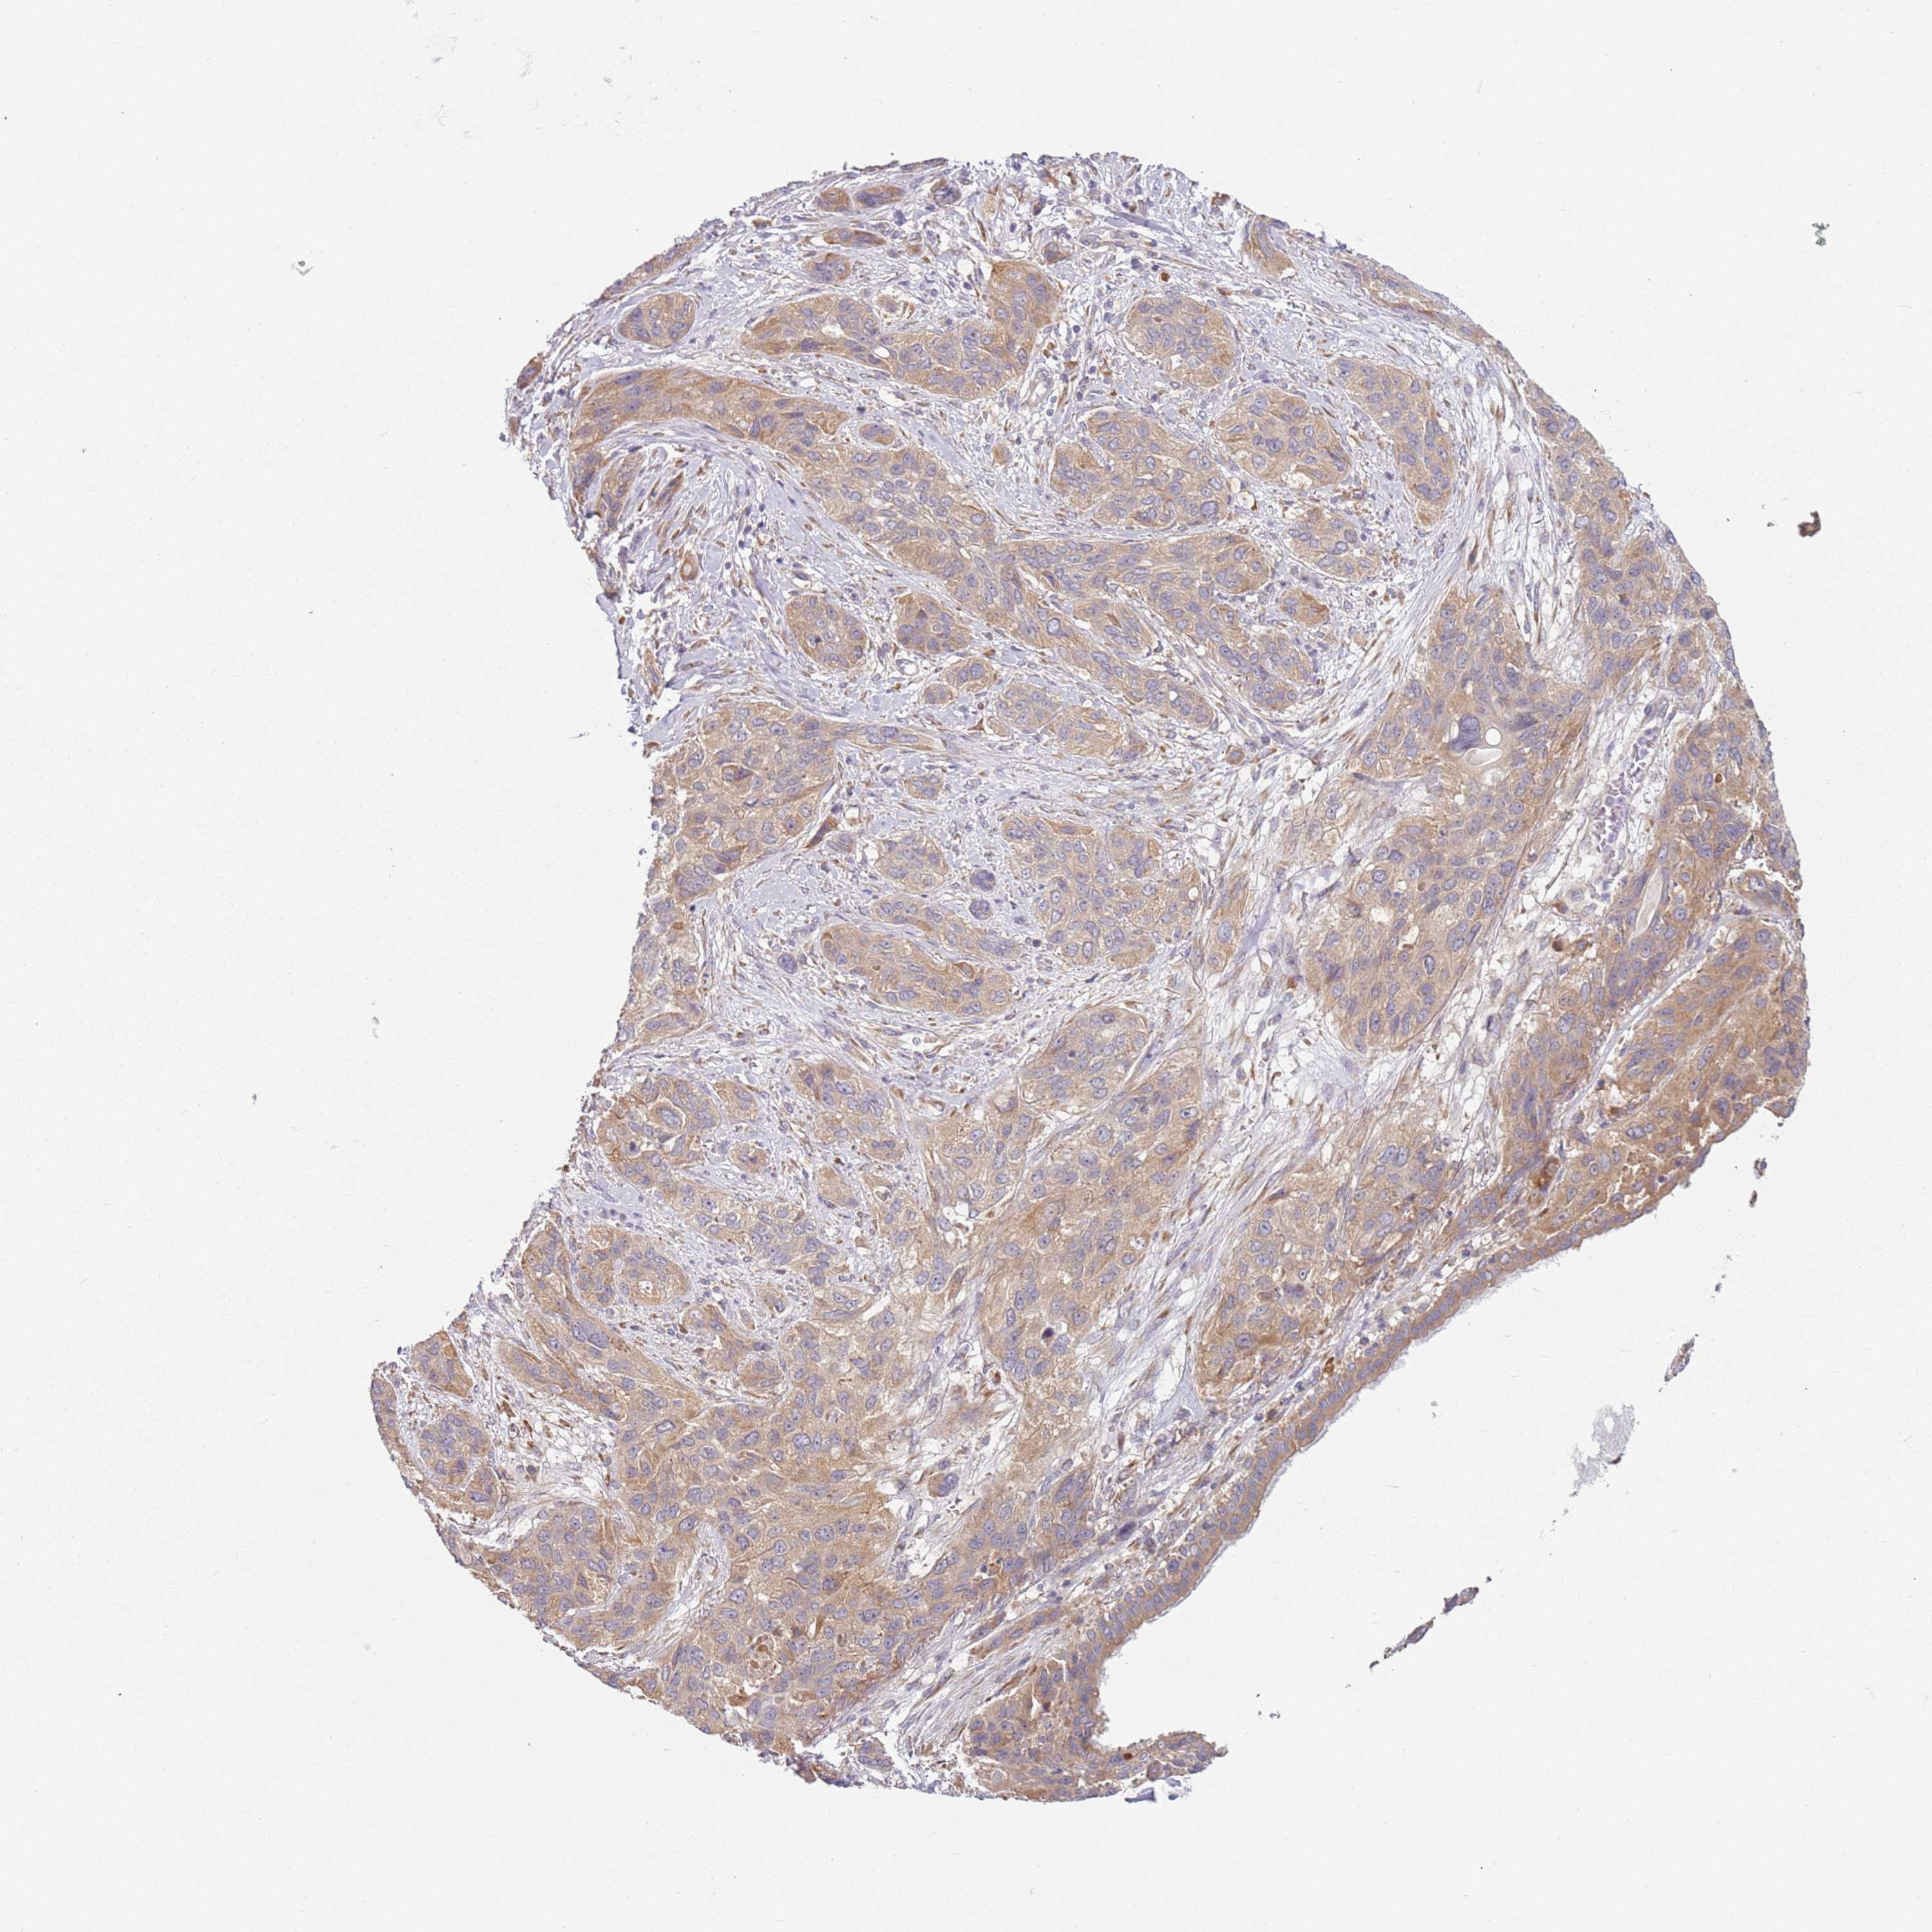

LUNG ADENOCARCINOMA (VALIDATION) - Interactive survival scatter ploti

The Survival Scatter plot shows the clinical status (i.e. dead or alive) for all individuals in the patient cohort, based on the same data that underlies the corresponding Kaplan-Meier plots. Patients that are alive at last time for follow-up are shown in blue and patients who have died during the study are shown in red.

The x-axis shows the expression levels (FPKM) of the investigated gene in the tumor tissue at the time of diagnosis. The y-axis shows the follow-up time after diagnosis (years). Both axes are complimented with kernel density curves demonstrating the data density over the axes. The top density plot shows the expression levels (FPKM) distribution among dead (red) and alive patients (blue). The right density plot shows the data density of the survived years of dead patients with high and low expression levels respectively, stratified using the cutoff indicated by the vertical dashed line through the Survival Scatter plot. This cutoff is automatically defined based on the FPKM cutoff that minimizes the p-score. The cutoff can be changed by dragging the vertical line or by entering a cutoff value in the square labeled "Current cut-off".

Under the Survival Scatter plot the p-score landscape (black curve; left axis) is shown together with dead median separation (red curve; right axis). Dead median separation is the difference in median mRNA expression between patients who have died with high and low expression, respectively. It is calculated as follows: median FPKM expression of dead patients with high expression - median FPKM expression of dead patients with low expression. This is intended to aid the user in visually exploring custom cutoffs and the associated p-scores and dead median separation.

Individual patient data is displayed and can be filtered by clicking on one or more of the category buttons on the top of the page. Categories describing expression level and patient information include: high, low, alive, dead, female, male and tumor stages. The scale of the x-axis can be toggled between linear and log-scale by clicking on the "x log" button. Mouse-over function shows TCGA ID, patient information and mRNA expression (FPKM) for each patient.

& Survival analysisi

Kaplan-Meier plots summarize results from analysis of correlation between mRNA expression level and patient survival. Patients were divided based on level of expression into one of the two groups "low" (under cut off) or "high" (over cut off). X-axis shows time for survival (years) and y-axis shows the probability of survival, where 1.0 corresponds to 100 percent.

RPS28 is not prognostic in Lung Adenocarcinoma (validation)

Stage:

Survival analysis

Current cut offi

Current cut-off shows the cut-off (FPKM) currently selected. It may be changed manually. When the current cut-off is changed, the vertical dashed line indicating cut-off, the interactive survival scatter plot and the Kaplan-Meier curve will be automatically adjusted to show results accordingly.

:

Best expression cut offi

Based on the FPKM value of each gene, patients were classified into two groups and association between prognosis (survival) and gene expression (FPKM) was examined. The best expression cut-off refers the FPKM value that yields maximal difference with regard to survival between the two groups at the lowest log-rank P-value. Best expression cut-off was selected based on survival analysis .

When clicking on this number, the vertical dashed line indicating cut-off, the interactive survival plot, and the Kaplan-Meier curve will be adjusted to show results based on the best expression cut-off.

: 55.28

Median expressioni

Median expression refers to the median FPKM value calculated based on the gene expression (FPKM) data from all patients in this dataset. When clicking on this number, the vertical dashed line indicating cut-off, the interactive survival plot, and the Kaplan-Meier curve will be adjusted to show results based on the median expression.

: N/A

Median follow up timei

Median follow up time refers to the median time (years) after diagnosis with this type of cancer, based on clinical data from all patients in this dataset.

P scorei

Log-rank P value for Kaplan-Meier plot showing results from analysis of correlation between mRNA expression level and patient survival.

N/A

5-year survival highi

5-year survival for patients with higher expression than the expression cutoff.

For melanoma and glioma, 3-year survival is shown.

5-year survival lowi

5-year survival for patients with lower expression than the expression cutoff.

TCGA RNA samplesi

RNA-seq data is reported as average FPKM (number Fragments Per Kilobase of exon per Million reads), generated by the The Cancer Genome Atlas (TCGA) .

Normal distribution across the dataset is visualized with box plots, shown as median and 25th and 75th percentiles. Points are displayed as outliers if they are above or below 1.5 times the interquartile range. FPKM values of the individual samples are presented next to the box plot.

Average pTPM 68.3

Number of samples 105